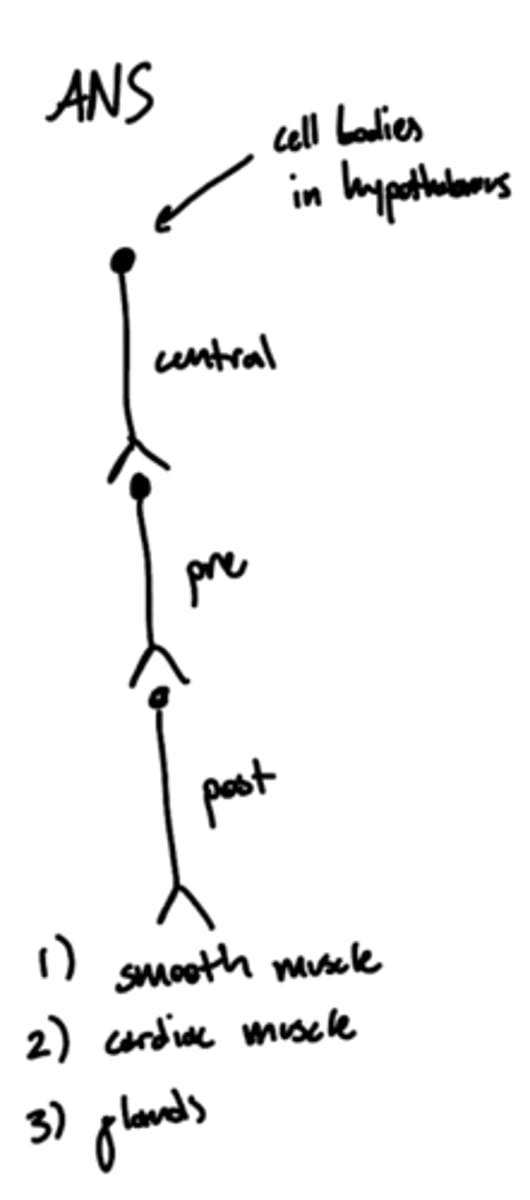

Where are the cell bodies of the central neurons of the autonomic nervous system?

hypothalamus